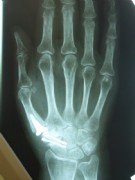

Middle and right: stiffening in the functional position with the V-tek regular screw. Eliminates pain and visually shows a satisfying result.

Below: End-joint stiffening in the index finger and middle-joint endoprosthesis in the middle finger